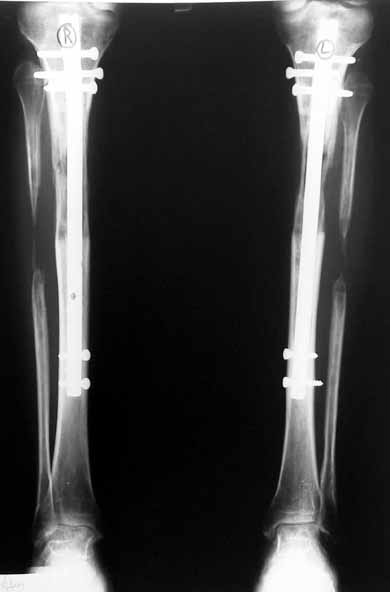

Biz son zamanlarda, seçilmiş vakalarda, uzatma sonrası uzunluğu ve “alignment’ı” korumak amacı ile unilateral dinamik aksiyel fiksatör ve kilitli intramedüller çivi kombinasyonunu tercih etmekteyiz. Bu yöntemin ön şartları medullanın en dar çapının 7 mm.’den geniş olması ve uzatma sonrası distalde en az 8 cm. uzunluğunda çivi kalabilmesidir. İntramedüller çivi hem uzatma esnasında femurun üzerine gelen makaslama ve bükülme kuvvetlerini nötralize etmekte hem eksternal fiksasyon süresini kısaltmakta, hem de yeni oluşan kemiği kırıklara karşı korumaktadır. Serimizde bir vakada subtrokanterik femoral osteotomi yapılmıştır. İntramedüller çiviye rağmen varus angulasyonu oluşması yönünde bir dezavantaj tespit etmedik.

İlizarov, distraksiyon osteogenezisi için endosteal kan dolaşımının önemini vurgulamıştır. Biz tüm vakalarımızda femuru oyarak intramedüller çiviyi çaktık; buna rağmen hiçbir vakada kallus oluşma süresi tahminimizden daha uzun olmadı. Bu yüzden medüller dolaşımın bozulmasına bağlı yeni kemik oluşma hızında bir yavaşlama olmadığını düşünüyoruz. Oyma sonrası meydana gelen revaskülarizasyon, intramedüller çivili fiksasyon stabilitesi ve erken fonksiyonel yüklenme bu gerçeğin temelini oluşturmaktadır. Eksternal ve internal fiksasyon yöntemlerinin kombine kullanımının potansiyel dezavantajları kan kaybının artması, intramedüller infeksiyon, yağ embolisi olasılığı ve aşırı metal yüküdür. Bunların içinde en çok korkulan problem bir çivi dibi infeksiyonun tetikleyeceği derin intramedüller infeksiyondur (panosteomyelit). Bizim serimizde bu yönde hiçbir komplikasyon gelişmemiştir. Bu olası komplikasyonun önlenmesi amacı ile uzatma sonundaki kilitleme medialden yapılmalıdır; ayrıca intramedüller çivi ve eksternal fiksasyon pinlerinin teması önlenmelidir.

Çocuklarda intramedüller çivi üzerinden uzatmanın bir diğer komplikasyonu olarak çivinin giriş yeri nedeni ile büyük trokanter apofizinin zedelenmesi ve sekonder koksa valga deformitesinin gelişmesi gösterilmektedir. Serimizdeki vakaların biri hariç tümü iskelet matüritesine erişmişlerdir. Oniki yaşında olan bir hastamızda son kontrolde koksa valga deformitesi saptanmamıştır. Vaka, halen takip edilmektedir.

İntramedüller çivi ve eksternal dinamik aksiyel fiksatör kombinasyonu teknik olarak standart İlizarov uygulamalarından daha zordur. Ancak şu avantajlar yöntemi cazip hale getirmektedir; eksternal fiksasyon süresinde kısalma, refraktüre karşı korunma, erken rehabilitasyon, azami hareket genişliği kazanma ve günlük yaşam konforu. Bu avantajlar artan maliyet , artan kan kaybı ve potansiyel derin infeksiyon gibi dezavantajların önüne geçmektedir. Sonuç olarak, bulgularımızın eşliğinde, intramedüller çivi üzerinden femoral uzatma tekniğinin güvenilir ve dayanıklı bir metod olduğunu ve bizce standart İlizarov uygulamalarına üstünlük sağlayan avantajlar getirdiğini söyleyebiliriz.